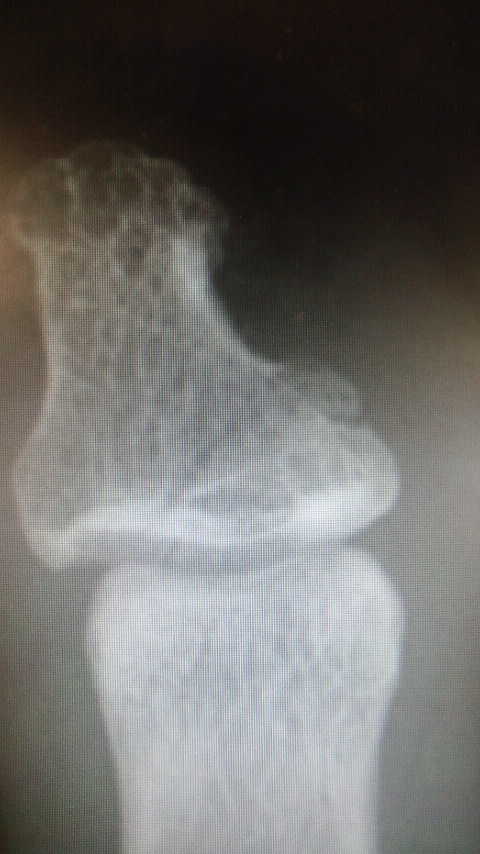

ついに麻酔科研修も終わり、今度は脳外科へ。 それにしてもマイクロのオペは辛い・・・w 足はだいぶよくなってきたけど、ふとした時にやっぱり痛い・・・。 でもウィンブルドン観てるとやっぱテニスしたくなるよね~。 ところで 今手持ちのPCは8年目のVAIO S(XP)と4年目のVAIO T(Vista)なんですが さすがにWindowsなら7が欲しくなってきたところ。 それに加えて この夏からdocomoのラインナップがスマホ1本に絞られたことを言い訳に ついにスマホにしちゃおうかなんて・・・。 そしたらやっぱりiPadなんかも欲しくなっちゃうわけで Macbook Pro+iPad2なんてのも・・・w うん、キリがないですなww しかしタブレットは使ってる人見てると便利そうよね・・・。 なんかおススメの組み合わせあります?? 今月からしばらく1月ごとのローテーション。 この調子だと2年目もあっという間だなぁ。 早く梅雨明けないかなぁ・・・ |